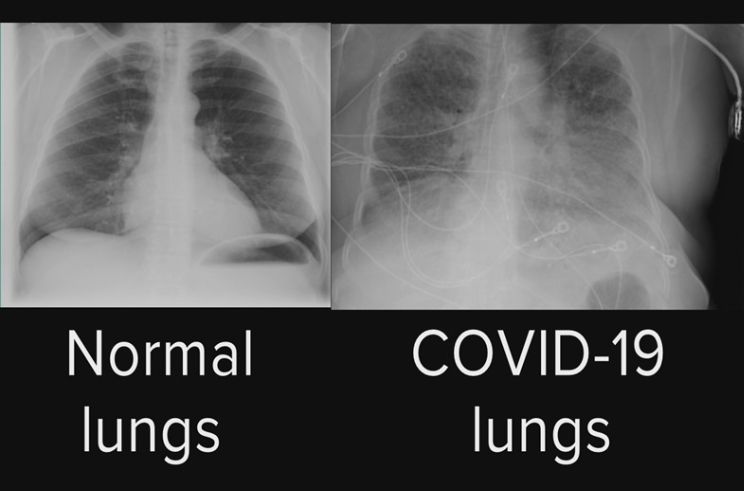

ตัวอย่างเช่น มลพิษทางอากาศ การสูบบุหรี่ โรคปอดบวม และโรคต่างๆ เช่น โรคหอบหืด โรคโควิด-19 และโรคปอดอุดกั้นเรื้อรัง (COPD) ล้วนมีส่วนทำให้การทำงานของปอดลดลง

นักวิจัยยังพบว่าการขาดวิตามินดีเกี่ยวข้องกับความรุนแรงของอาการปอด ระยะเวลาของโรคที่ยาวนานขึ้น และความเสี่ยงต่อการเสียชีวิตที่สูงขึ้นในผู้ป่วย COVID-19 ที่เข้ารับการรักษาในโรงพยาบาล และการขาดวิตามินดีอาจเพิ่มความเสี่ยงต่อ COVID-19

การขาดซีลีเนียมและสังกะสีอาจเพิ่มความเสี่ยงต่อการติดเชื้อทางเดินหายใจ เช่นเดียวกับความเสี่ยงต่ออาการรุนแรงและการเสียชีวิตในผู้ป่วย COVID-19 และอาจเพิ่มความเสี่ยงต่อการเกิดมะเร็งปอด